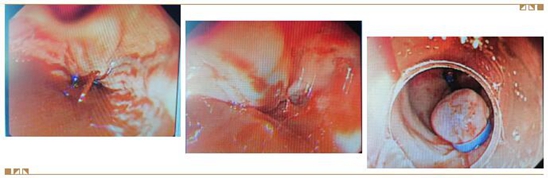

操作由胃肠肝胆学科部邢国辉医生执行,胃镜刚进入食管即见大量的鲜血,冲洗后露出多条面目峥嵘的曲张静脉,继续进镜至食管下段,即见一条粗大的静脉破裂,鲜血正从破口处喷射而出(左图),这时心电监护显示收缩压下降至70mmHg,心率达130次/分,病人已处于失血性休克状态,情况紧急,邢国辉当机立断,决定立即给予栓塞止血治疗,助手董磊娴熟的将组织胶粘合剂注入血管破口处,出血随即戛然而止(中图),整个手术过程不到3分钟。术后继续输液等治疗,患者心率、血压很快恢复正常,后期给予剩余的曲张静脉行胃镜下套扎治疗(右图),使曲张的血管消失,防治再次发生血管破裂出血。目前病人正在顺利恢复中。